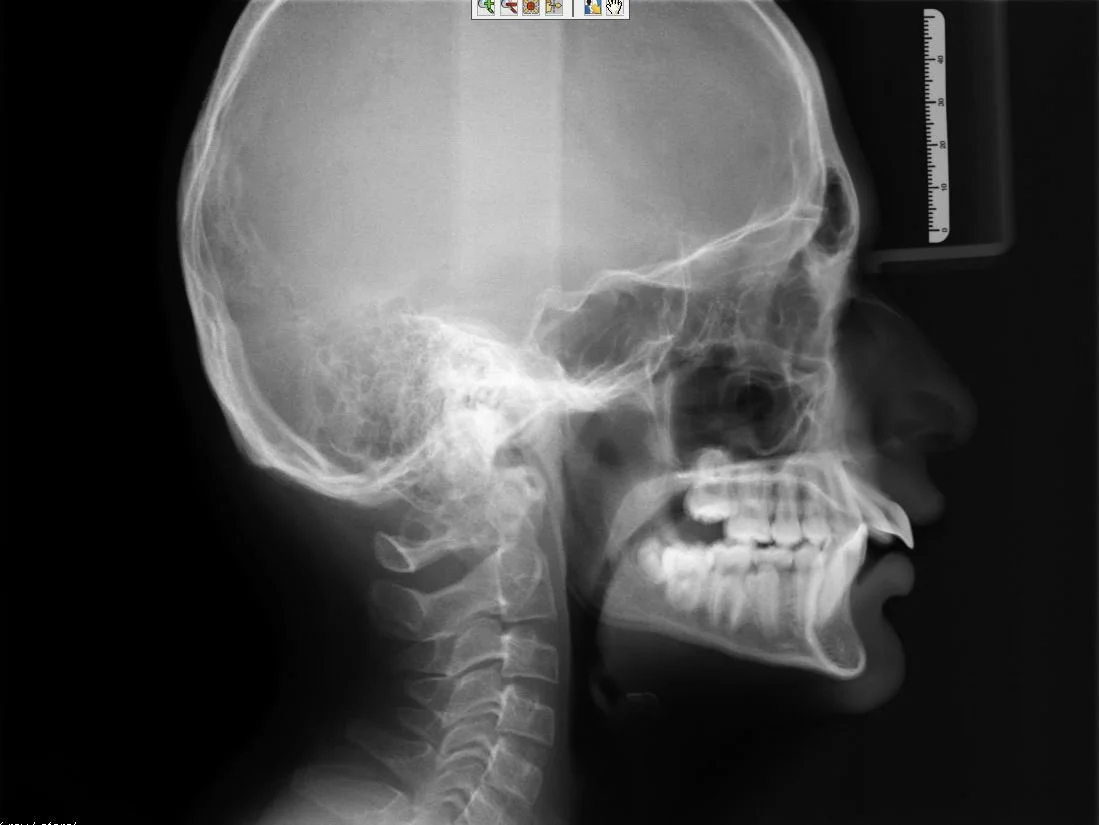

ceph class 2 retrognathic.JPG